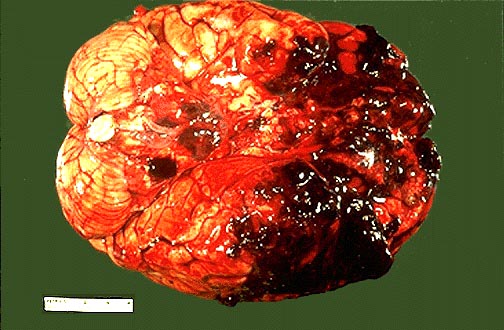

对冲性颅脑损伤非常多见。受伤原因虽多, 但大部分是由于外力作用使伤者后仰头枕部着力所致, 即当运动头部撞于物体时, 颅骨运动立即停止, 但脑组织由于惯性仍沿着原方向继续运动, 此时脑组织被惯力压缩, 作用点的对侧部位即额颞叶脑与脑膜之间产生间隙形成负压, 撕裂脑皮层引流静脉致硬膜下出血, 由于反作用力使脑组织瞬间反弹,额极与额骨内面撞击、额底与眶底粗糙面摩擦、颞叶前端撞击于蝶骨嵴处、致脑皮层挫裂伤; 再由于脑组织受到剧烈错动脑内神经纤维及血管撕裂、垂体柄受牵拉、桥脑撞击于斜坡, 因而发生多处脑组织伤,临床症状严重复杂。